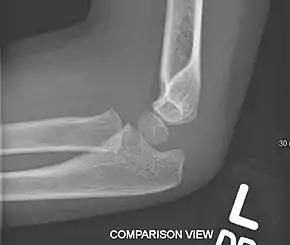

Fractured elbow in a child (ulnar shaft) with joint effusion of elbow

Normal elbow in same child, other side